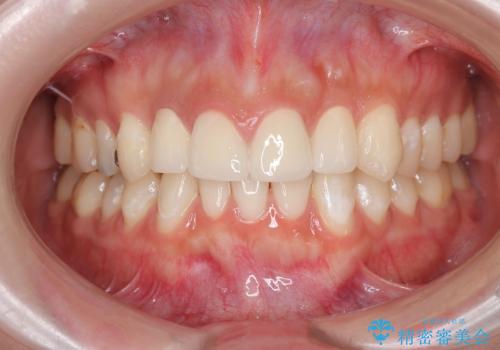

充填物の変色を繰り返す前歯のセラミック治療

- 神経をとった前歯の変色や、前歯の充填物の変色が大きくなってきたので審美性の改善を求めて来院されました。

充填物や充填物下に再発した虫歯を丁寧に除去し、セラミッククラウンによる審美性の改善、虫歯治療を計画します。

- 52.8万円(ジルコニアクラウン×4・仮歯×4)費用は治療当時の料金となります